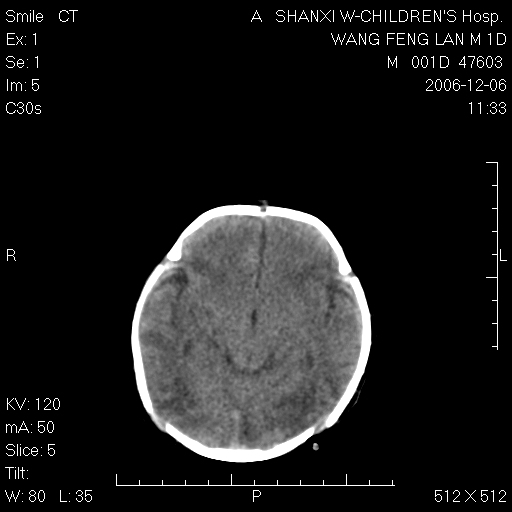

以下是引用husiling在2006-12-6 18:14:00的发言:[br]1\\hie[br]2\\蛛血.

以下是引用zjzjr在2006-12-6 19:29:00的发言:[br]支持新生儿缺血缺氧性脑病伴少量蛛网膜下腔出血.

以下是引用卜一在2006-12-6 21:38:00的发言:[br][br] 支持:新生儿缺血缺氧性脑病伴少量蛛网膜下腔出血 [br]